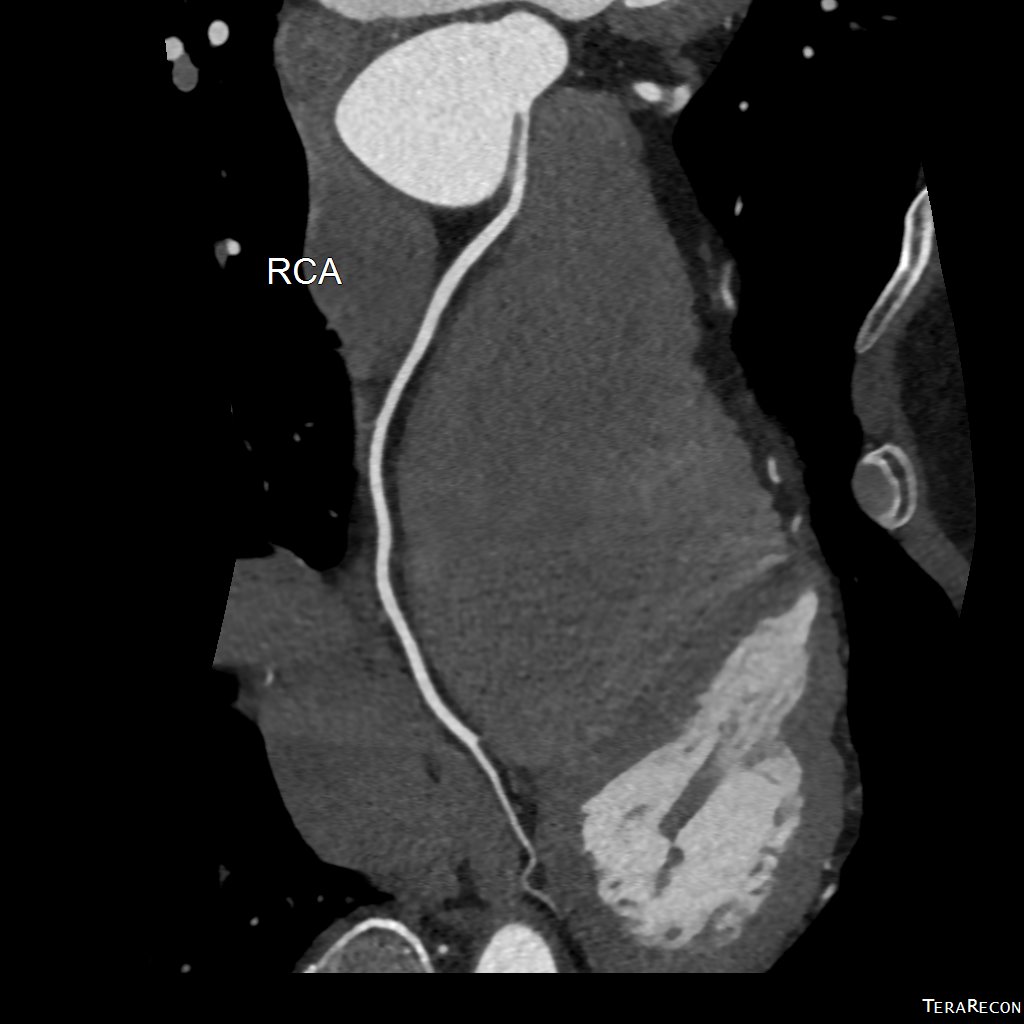

冠狀動脈電腦掃描造影

(CT Coronary Angiogram)

冠狀動脈CT造影 是目前評估心血管疾病風險的重要非入侵性工具,可:

• 清楚顯示冠狀動脈有否出現狹窄、阻塞或鈣化

• 為懷疑有心絞痛或心肌缺血的患者提供早期診斷依據

• 協助心臟科醫生決定是否需進一步介入性治療,如通波仔(PCI)